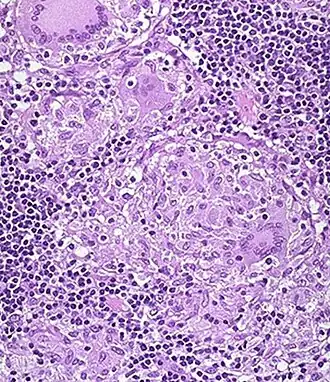

Ziarniniak (niepoprawne: ziarniak; łac. granuloma) – zgrupowanie epitelioidalnych makrofagów oraz innych komórek zapalnych i należących do układu odpornościowego, a także macierzy pozakomórkowej[1], zwykle otoczone przez mankiet limfocytów.

Ziarniniaki są małymi grudkami występującymi na przykład w chorobie Leśniowskiego-Crohna, gruźlicy, trądzie, sarkoidozie, berylozie, kile, chorobie kociego pazura oraz ziarniniakowatości z zapaleniem naczyń i zespole Churga-Strauss (powiązanych chorobach autoimmunizacyjnych).